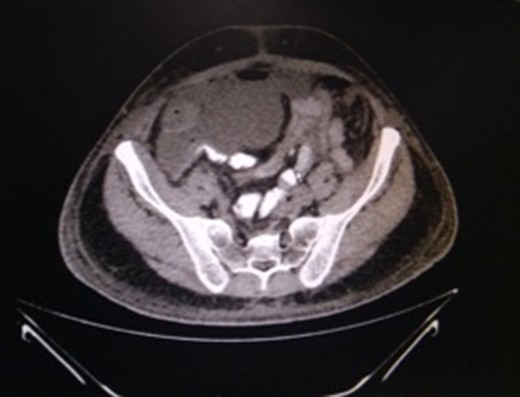

This 50-year-old male had, 4 months previously, undergone an anterior resection of a recto-sigmoid adenocarcinoma, non-anatomical resection of a liver metastasis and diverting loop ileostomy. The pathological report was a moderately differentiated adenocarcinoma and he subsequently received seven cycles of adjuvant chemotherapy. Two weeks after the last chemotherapy cycle he had a contrast study through the distal limb of his ileostomy which was normal. He then underwent a side-to-side hand sewn ileo-ileal anastomotic closure and started passing flatus and stools from the third postoperative day (POD). On POD 4 however he developed lower abdominal distension and a plain X-ray of the abdomen revealed air to be present in the colon and rectum with a few prominent small bowel loops. He then developed massive painless penoscrotal swelling, On local examination the genitals were not tender and there was no elevation of the local temperature (penoscrotal oedema image, Fig. 1). Blood investigations revealed a haemoglobin level of 12.8 g/dl, total leucocyte count of 5900/mm3, serum creatinine of 0.85 mg/dl, total protein 5.18 g/dl and albumin 2.95 g/dl. A urologist’s opinion was sought who opined that the patient might be having common iliac vein thrombosis but a Doppler study of the lower limb and pelvic veins was normal. However the abdominal distension persisted although he was passing flatus and stools. CECT of the abdomen was done on POD-6 and this revealed a large irregular air containing collection extending from the right subhepatic region along the paracolic gutter into the pelvis as well as a fluid collection in the lesser sac extending along the greater curvature of the stomach (CT images). Three percutaneous drains were then inserted—one each in the subhepatic region, pelvis and the left lesser sac and 1500 ml of faeculent content was removed. The patient was kept nil by mouth, started on parenteral nutrition and his antibiotics were upgraded. Over the next 3 days the effluent decreased and the fluid became serous. The penoscrotal oedema also subsided after 4 days (Figs 2–5). On POD-12, a CT scan of the abdomen with oral contrast was done again (CT images), which showed a decreased size of the collection and no well-defined area of extravasation or leak of contrast outside the bowel lumen. The drains were then removed, he was started on oral liquids and later put on a soft diet and discharged on POD-20.

CT-abdomen showing pelvic collection. Source: Department of Radiology, Sir Ganga Ram Hospital, New Delhi.